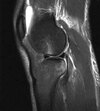

* Sagittal MRI images showing meniscal continuity in three 5mm sagittal images (“bow-tie sign”) is diagnostic.

* If there is pain, mechanical symptoms, meniscal tear or detachment, arthroscopic debridement and saucerization is indicated. The aim is to preserve a rim of normal meniscus.